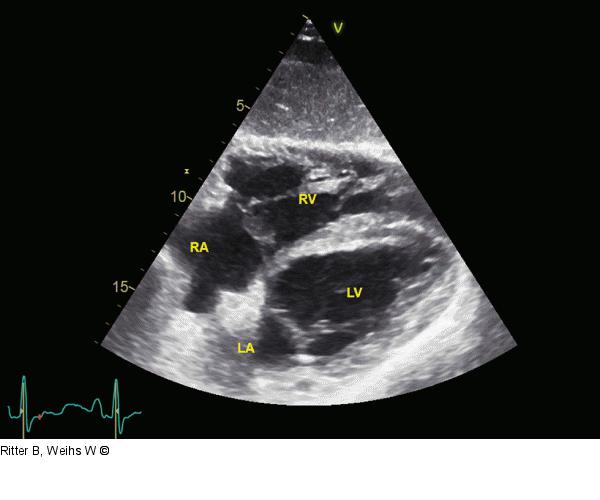

Abbildung 5: Rechtsventrikuläre Pumpfunktion Gleichzeitig signifikante Abnahme der rechtsventrikulären Größe und deutlich bessere Kontraktilität. RA: rechter Vorhof; RV: rechter Ventrikel; LV: linker Ventrikel; LA: linker Vorhof |

Gleichzeitig signifikante Abnahme der rechtsventrikulären Größe und deutlich bessere Kontraktilität. RA: rechter Vorhof; RV: rechter Ventrikel; LV: linker Ventrikel; LA: linker Vorhof |